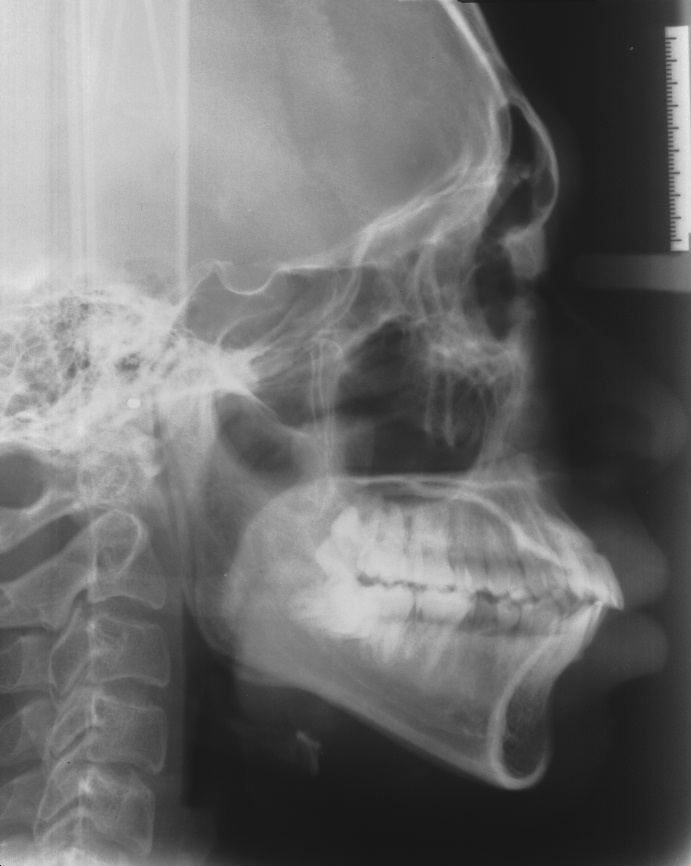

[돌출입] 돌출입